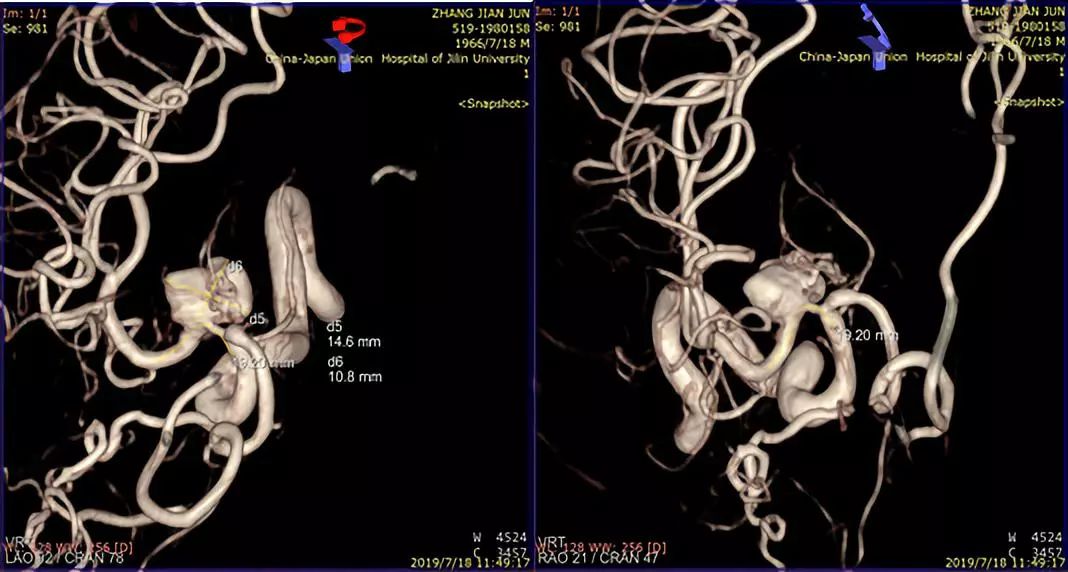

术前造影:

治疗颅内动脉瘤新型密网支架,pipeline治疗椎动脉夹层动脉瘤

此患者为一53岁的男性患者,因发现右侧大脑中动脉M1段动脉瘤2周而住院治疗。从患者影像学资料分析,患者动脉瘤的形态学很不稳定,而且有明显增大的趋势,血流滞留很明显,考虑夹层动脉瘤可能性较大。患者有头痛的病史,对比两周前的影像资料,动脉瘤有增大趋势。患者治疗意愿比较强烈。造影结果显示,患者夹层动脉瘤上方有一较大的分支动脉—豆纹动脉。请神经外科会诊,会诊意见:手术干预难以保留豆纹动脉,开颅手术不具有治疗优势。与患者及患者家属沟通后,患者及患者家属积极要求介入治疗。

术前讨论:如何使患者获得最大受益?因为是夹层动脉瘤,如果填圈治疗,一是外侧豆纹动脉会即刻闭塞,更易引起临床症状;二是填圈治疗有使夹层动脉瘤撕开、出血的风险。所以经讨论我们决定采取一种折中方案,只放密网支架而不填圈的手术方式。我们希望通过密网支架的支撑,使夹层动脉瘤慢慢消失。通过慢性闭塞,给夹层动脉瘤上方的豆纹动脉部位一个代偿血管增生的时间,减少患者发生偏瘫的概率。经过精准测量后,选择合适支架。术中手术顺利,术后进行血管三维重建,密网支架放置良好,贴壁良好,可以清晰的看到豆纹动脉。术后患者回到病房后,一般情况良好。术后18小时后患者出现言语含糊、左侧中枢性面舌瘫,左侧肢体偏瘫,CT排查出血后考虑是患者夹层动脉瘤上方的豆纹动脉闭塞引起的症状。立即行全脑血管造影,发现豆纹动脉确实消失。确定豆纹动脉消失是引起患者临床症状的一个主要原因。这是天坛医院第一例在密网支架植入术后第一天就复查造影的患者。造影结果让我们惊喜的发现,密网支架治疗后,不到18个小时,患者的动脉瘤几乎完全消失。从而证明,我们的手术通过精准测量,选择合适的密网支架对夹层动脉瘤的治疗效果以及夹层的修复效果是非常明显的。当然,患者出现穿支动脉的闭塞,是我们术前充分考虑的,且无法避免的一个并发症。术后给予神经康复,高压氧治疗,患者有明显的好转趋势。我们希望通过后续的康复治疗可以使患者的生活接近正常,同时我们也在密切随访患者,希望患者动脉瘤完全消失,并且正常生活。